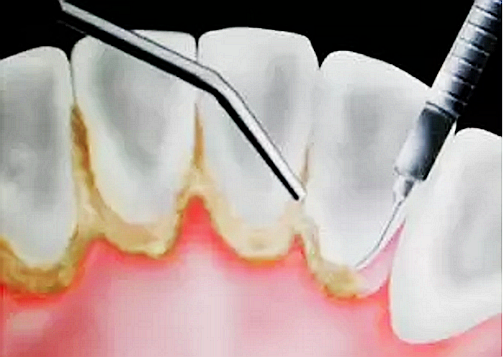

很多人會有這樣的疑問,為什么有時候到醫(yī)院檢查牙齒后醫(yī)生會建議我們做牙周刮治?為什么做完常規(guī)的潔牙(洗牙)后,還需要進行更深層次的牙周刮治呢?

首先,必須弄清楚支持牙齒的牙周組織組織(牙齦和牙槽骨)的健康狀況。牙周組織的健康與堆積在牙齒上的牙菌斑(較軟)和牙結(jié)石(較硬)的數(shù)量密切相關(guān)。

對大多數(shù)的人來說,去醫(yī)院潔牙時,牙齒上的牙菌斑基本上已發(fā)展成為了牙結(jié)石。牙結(jié)石最容易沉積的部位就是下前牙的舌側(cè)和上后牙的頰側(cè)。

定期潔牙的人也會有不同程度的牙結(jié)石堆積,間隔的時間越長,堆積的牙結(jié)石就會越來越厚越大。

牙結(jié)石首先在牙齒與牙齦的交界處沉積,如果堆積的牙結(jié)石沒有及時去除,面積會越來越大,并朝著牙齦下發(fā)展,導致牙齦炎癥。牙齦炎癥會引起牙齦腫痛,這種腫痛感就像皮膚被針刺一樣。

由于不使用牙線、刷牙方式的不正確,或者其他因素(如牙列不齊、口腔內(nèi)有不良修復體、藥物作用、激素水平的變化)的影響,也許一個人只有牙齦上的結(jié)石,沒有牙槽骨吸收的現(xiàn)象,此時只需常規(guī)的潔牙。

當牙齦下存在的牙結(jié)石,或有牙槽骨吸收跡象時,常規(guī)潔牙往往無法清除牙齦下的結(jié)石,此時需要進行牙周刮治了。